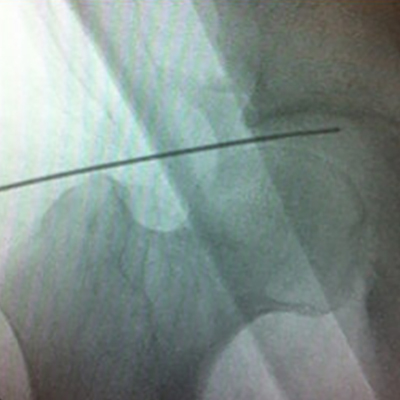

Imágenes de Artroscopía de Cadera